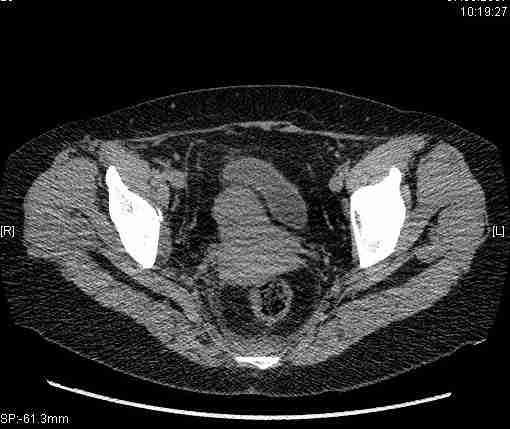

Женщина,58 лет, после ДТП 6 суток. Первично повреждение расценено как переломы ветвей лонной кости. После подтверждения повреждения вертлужной впадины,как чаще всего случается, вопрос встал о тактике. БОльшинство за консерватиное лечение.К сожалению кт у нас "во время" сломался. Прилагаю стандартные снимки вертлужки. У меня следующие вопросы к коллегам:1. Правильно ли рассценивать это повреждение как Т-образный перелом вертлужнй впадины?2. Можно ли добиться анатомической репозиции поверхности вертлужной впадины скелетным вытяжением в данном случае, если нет, что будет этому препятствовать?3. Если смещение останется таким как сейчас, через какое время появится необходимость эндопротезирования (по вашему опыту)?Спасибо.

Удалось сегодня вывести пациентку в соседнюю больницу, где есть кт. Срезы сделаны только горизонтальные.

|